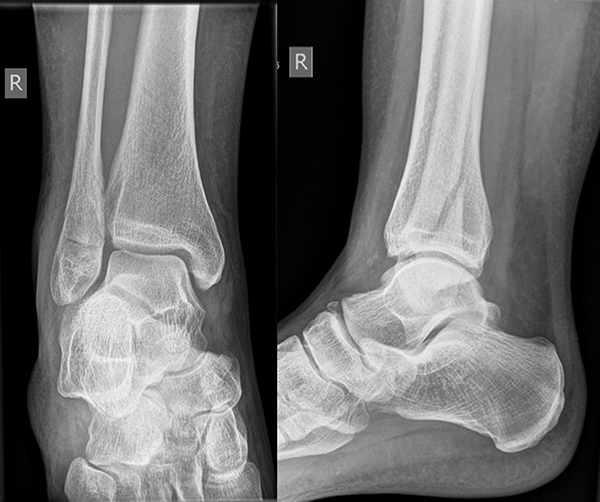

Die Standard-Röntgenaufnahmen des oberen Sprunggelenks bestehen aus drei Aufnahmen: der antero-posterioren Aufnahme (ap), der antero-posterioren Aufnahme mit Innenrotation des Unterschenkels von 20° („Mortise view“), sowie der streng seitlichen Aufnahme (siehe S2-Leitlinie Sprunggelenksfraktur). In der Röntgen-Bildgebung sollte neben den klassischen Frakturzeichen die Integrität der Syndesmose beurteilt werden. Dies erfolgt über die Beurteilung der Breite des lateralen und medialen Gelenkspalts („medial clear space“), des tibiofibularen Abstands 1cm oberhalb des OSG-Gelenkspalts („tibiofibular clear space“), bzw. der tibiofibularen Überlappung. Eine Verbreiterung des tibiofibularen Abstands über 5 mm oder die Erweiterung des medialen Gelenkspalts können Zeichen einer begleitenden Syndesmosenverletzung sein. (Abbildung 3) 6.

Liegt eine Fraktur des oberen Sprunggelenks vor, ist sowohl zur Entscheidung für ein konservatives oder operatives Vorgehen, als auch zur Operationsplanung, ein ausreichendes Verständnis der Fraktur und ihrer Morphologie notwendig. Insbesondere bei komplexen Verletzungen ist dafür die konventionelle Röntgenaufnahme in vielen Fällen nicht ausreichend. So konnten z.B. Black et al. zeigen, dass die operative Strategie zur Versorgung von OSG-Frakturen in 24% basierend auf einer zusätzlichen CT-Bildgebung relevant geändert wurden 7. Dies betraf die Lagerung, die Wahl des Zuganges und die Art der osteosynthetischen Versorgung. Besonders häufig änderte sich das Vorgehen bei Verletzungen des medialen (21%) und des posterioren Malleolus (15%). Darüber hinaus führten dislozierte (dislozierte Frakturen 31% vs. nicht-dislozierte Frakturen 20%) oder komplexe Frakturen (Trimalleolar-Frakturen 29% vs. Unimalleolar-Frakturen 10%) besonders häufig zu relevanten Änderungen des operativen Vorgehens. Die Computertomographie ist daher, insbesondere bei Bi- und Trimalleolar-Frakturen, essentiell für das Verständnis der Fraktur und somit für die Planung und Durchführung der Operation. In Abbildung 4 und 5 sind exemplarisch ein Röntgen- und ein CT Befund gegenübergestellt.